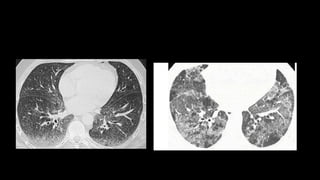

• In early stages, the only HRCT abnormality may be fine reticulation

• Honey combing 3mm to 2 cm, 3 in a row

• reticular opacities

• traction bronchiectasis

• subpleural and lower lobe predominance

• GGOs are rare

UIP pattern

• 1. Subpleural and basal predominance

• 2. Reticular abnormality

• 3. Honeycombing with or without traction

bronchiectasis

• 4. Absence of inconsistent features